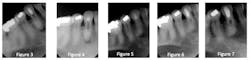

The case presented involves a mandibular canine that not only had a devitalized pulp, but also demonstrated a canal that had calcified for unknown reasons (Figs. 1 and 2). In addition to an asymptomatic periapical lesion, the patient presented with an extraoral fistula.

Several attempts at negotiating the canal were unsuccessful (Figs. 3 and 4), but after each visit, a thick mix of calcium hydroxide was densely packed into the preparation (Fig. 5). After approximately nine months, the lesion was seen to have resolved solely through the chemical reduction in the “bio load” present in the root canal system. The artificially created canal was then sealed with glass ionomer, followed by composite (Fig. 6). Of note, there is no sealer and no gutta percha anywhere in this tooth! One-year radiographic follow-up shows complete healing of the apical lesion (Fig. 7).